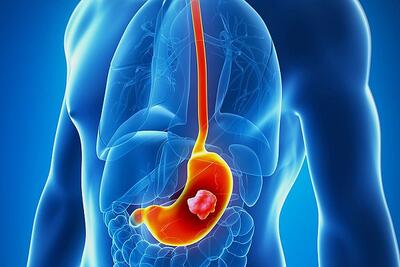

رد پای یک میکروب خطرناک در ماکارونی! + اینفوگرافیک